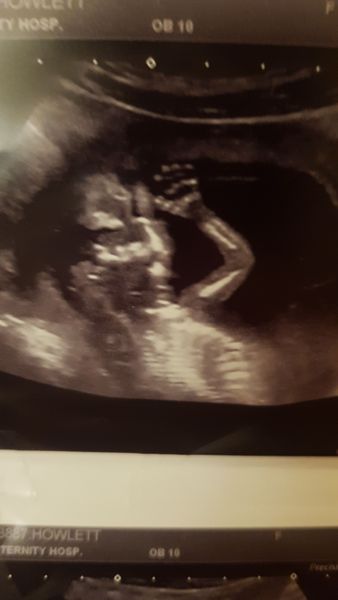

Hey everyone had my scan been dated one day less than I thought. But still amazing baby playing away waving hands was amazing to see!!!

Due date 16th August

@Chocolate89 loving your scan ! Baby is waving!!